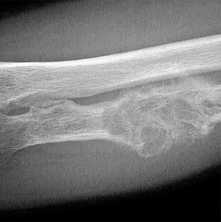

- Деструкция с «разъеданием» костной структуры на рентгенограммах выглядит как дефект - «дырка», такой вариант метастазирования называют остеолитическим, что буквально означает «съеденная кость».

- При утолщении кости за счёт опухоли рентгенограмма выявляет «плюс ткань», тогда говорят об остеопластическом метастазировании.

- Как правило, у больного встречаются оба вида метастазов с превалированием одного из вариантов, в большинстве случаев остеолитического.

По клинико-рентгенологическим признакам все костные очаги подразделяют на три группы:

- остеобластические — с преобладанием уплотнения сверх физиологической меры, но дополнительно наросшая опухолевая ткань не придаёт кости прочности и может сдавливать проходящие по соседству нервы;

- остеолитические — превалирует разрушение структуры и вероятность перелома увеличивается по мере разрастания рака;

- смешанные — сочетание двух видов и это ситуация встречается чаще всего.

Практически не случает такого, чтобы у пациента были исключительно остеолитические или только остебластические очаги, как правило, диагностируется сочетание с превалированием либо разреженной литической, либо избыточной бластической структуры.